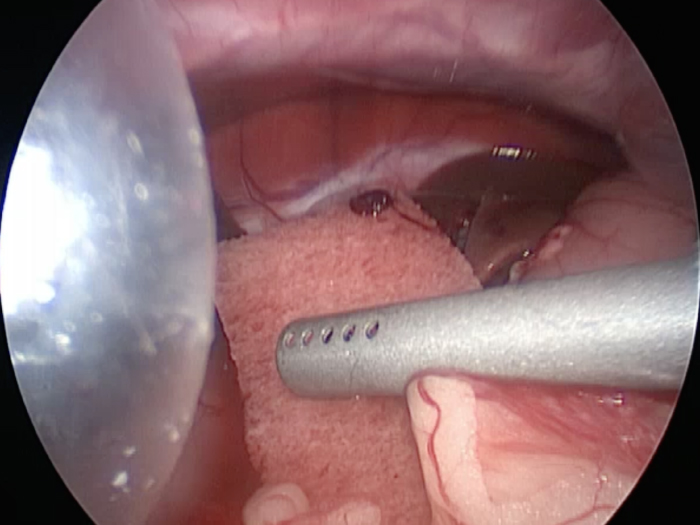

犬4kg。犬の腹腔鏡下胆嚢摘出術。症例は非常に癒着がひどく胆嚢を剥離するのが大変だった。 4ポートでの摘出となったが出血は少なく摘出が可能であった。 CLARA&CROMAという新しいモードで手術している。 これは暗いところ明るくし、CROMAは赤を強くしコントラストをつけることにより血管一本までしっかりと確認することができる。 少しギラギラするが、手術しやすくなる。

胆嚢の周囲の脂肪や膵臓、十二指腸が激しく癒着し剥離が困難な状態でした。 胆嚢は全く確認することができませんでした。

少しずつ癒着を剥がして胆嚢が確認できるようになってきました。

こんなに癒着していることはあまりないので過去に膵炎や胆嚢炎を起こし苦しい時期があったことが推測されました。

それにしてもなかなか胆嚢はでてきませんでした。

手術は丁寧に剥離していったため時間がかかってしまいました。

症状がなかったので、こんなに大変な状態になっているとは。

癒着(矢印)がひどく胆嚢を確認することができませんでした。

このように癒着しているときはギリギリで剥がすとひどく出血をおこすことがあるので無理にはがそうとしないで、脂肪の血管に注意しながら脂肪ごと剥がしていきます。